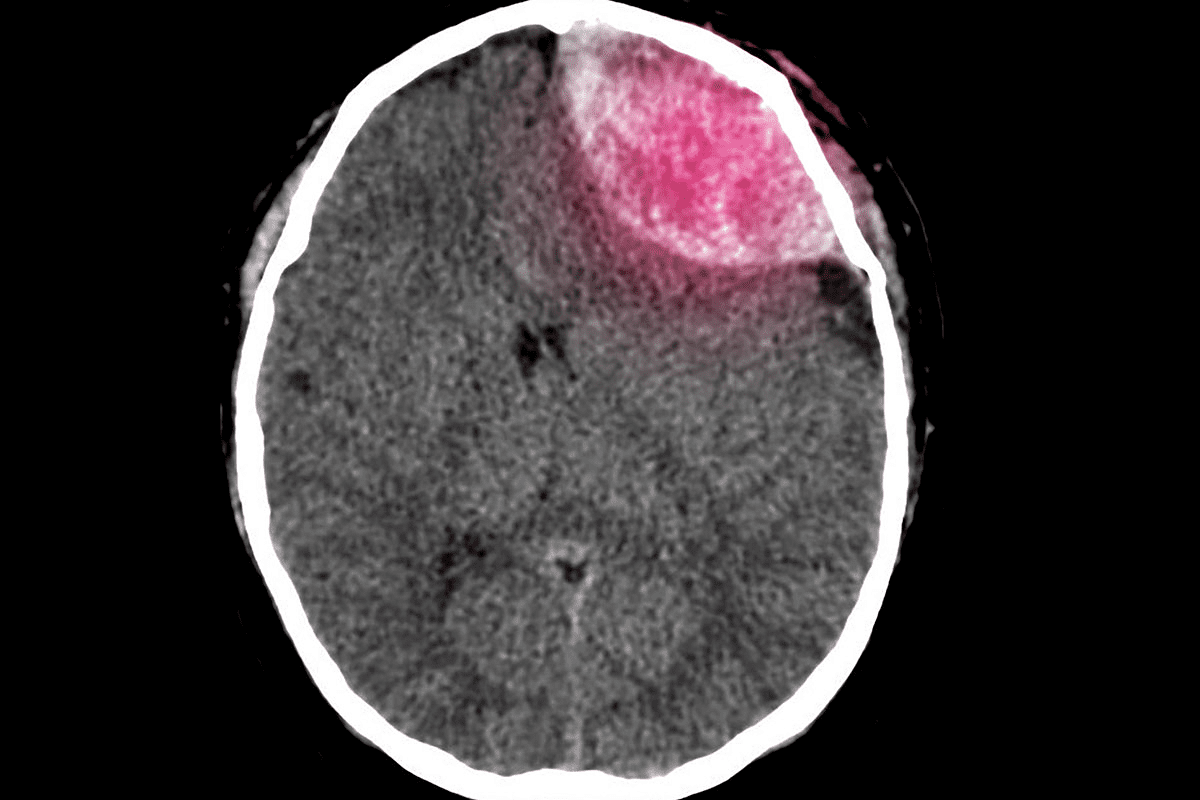

What is a Pituitary Tumor Craniotomy?

Understanding craniotomy for pituitary tumors is key for patients. A craniotomy is a surgery where part of the skull is removed to access the brain. This method helps surgeons reach tumors that are big or complex.

Definition and Purpose

A pituitary tumor craniotomy is a surgery where the skull is partially removed to get to the pituitary gland. The main goal is to remove the tumor safely without harming nearby important areas. This is especially useful for big tumors or those putting pressure on the brain.

This surgery aims to remove the tumor safely, reducing the risk of damage. The choice to do a craniotomy depends on the tumor’s size, location, and the patient’s health.

When is a Craniotomy Recommended

A craniotomy is usually suggested for patients with:

- Large or giant tumors

- Complex or irregularly shaped tumors

- Tumors causing a lot of pressure on the brain

- Tumors not responding to other treatments

According to the American Cancer Society, craniotomy is often chosen for bigger or more complex tumors. These can’t be safely removed through other methods.